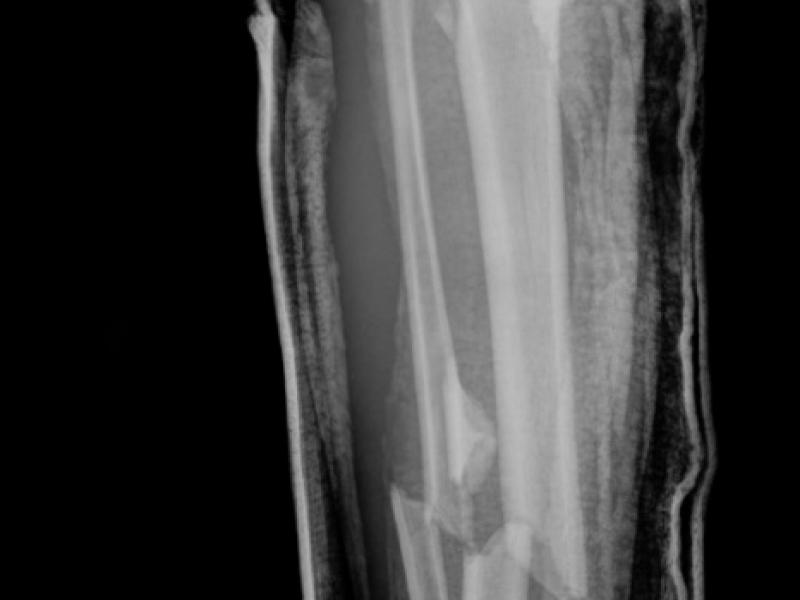

Critical Cases: Not Just an Ankle Sprain! Demystifying the Maisonneuve Fracture

0715: A patient arrives in the ED complaining of medial